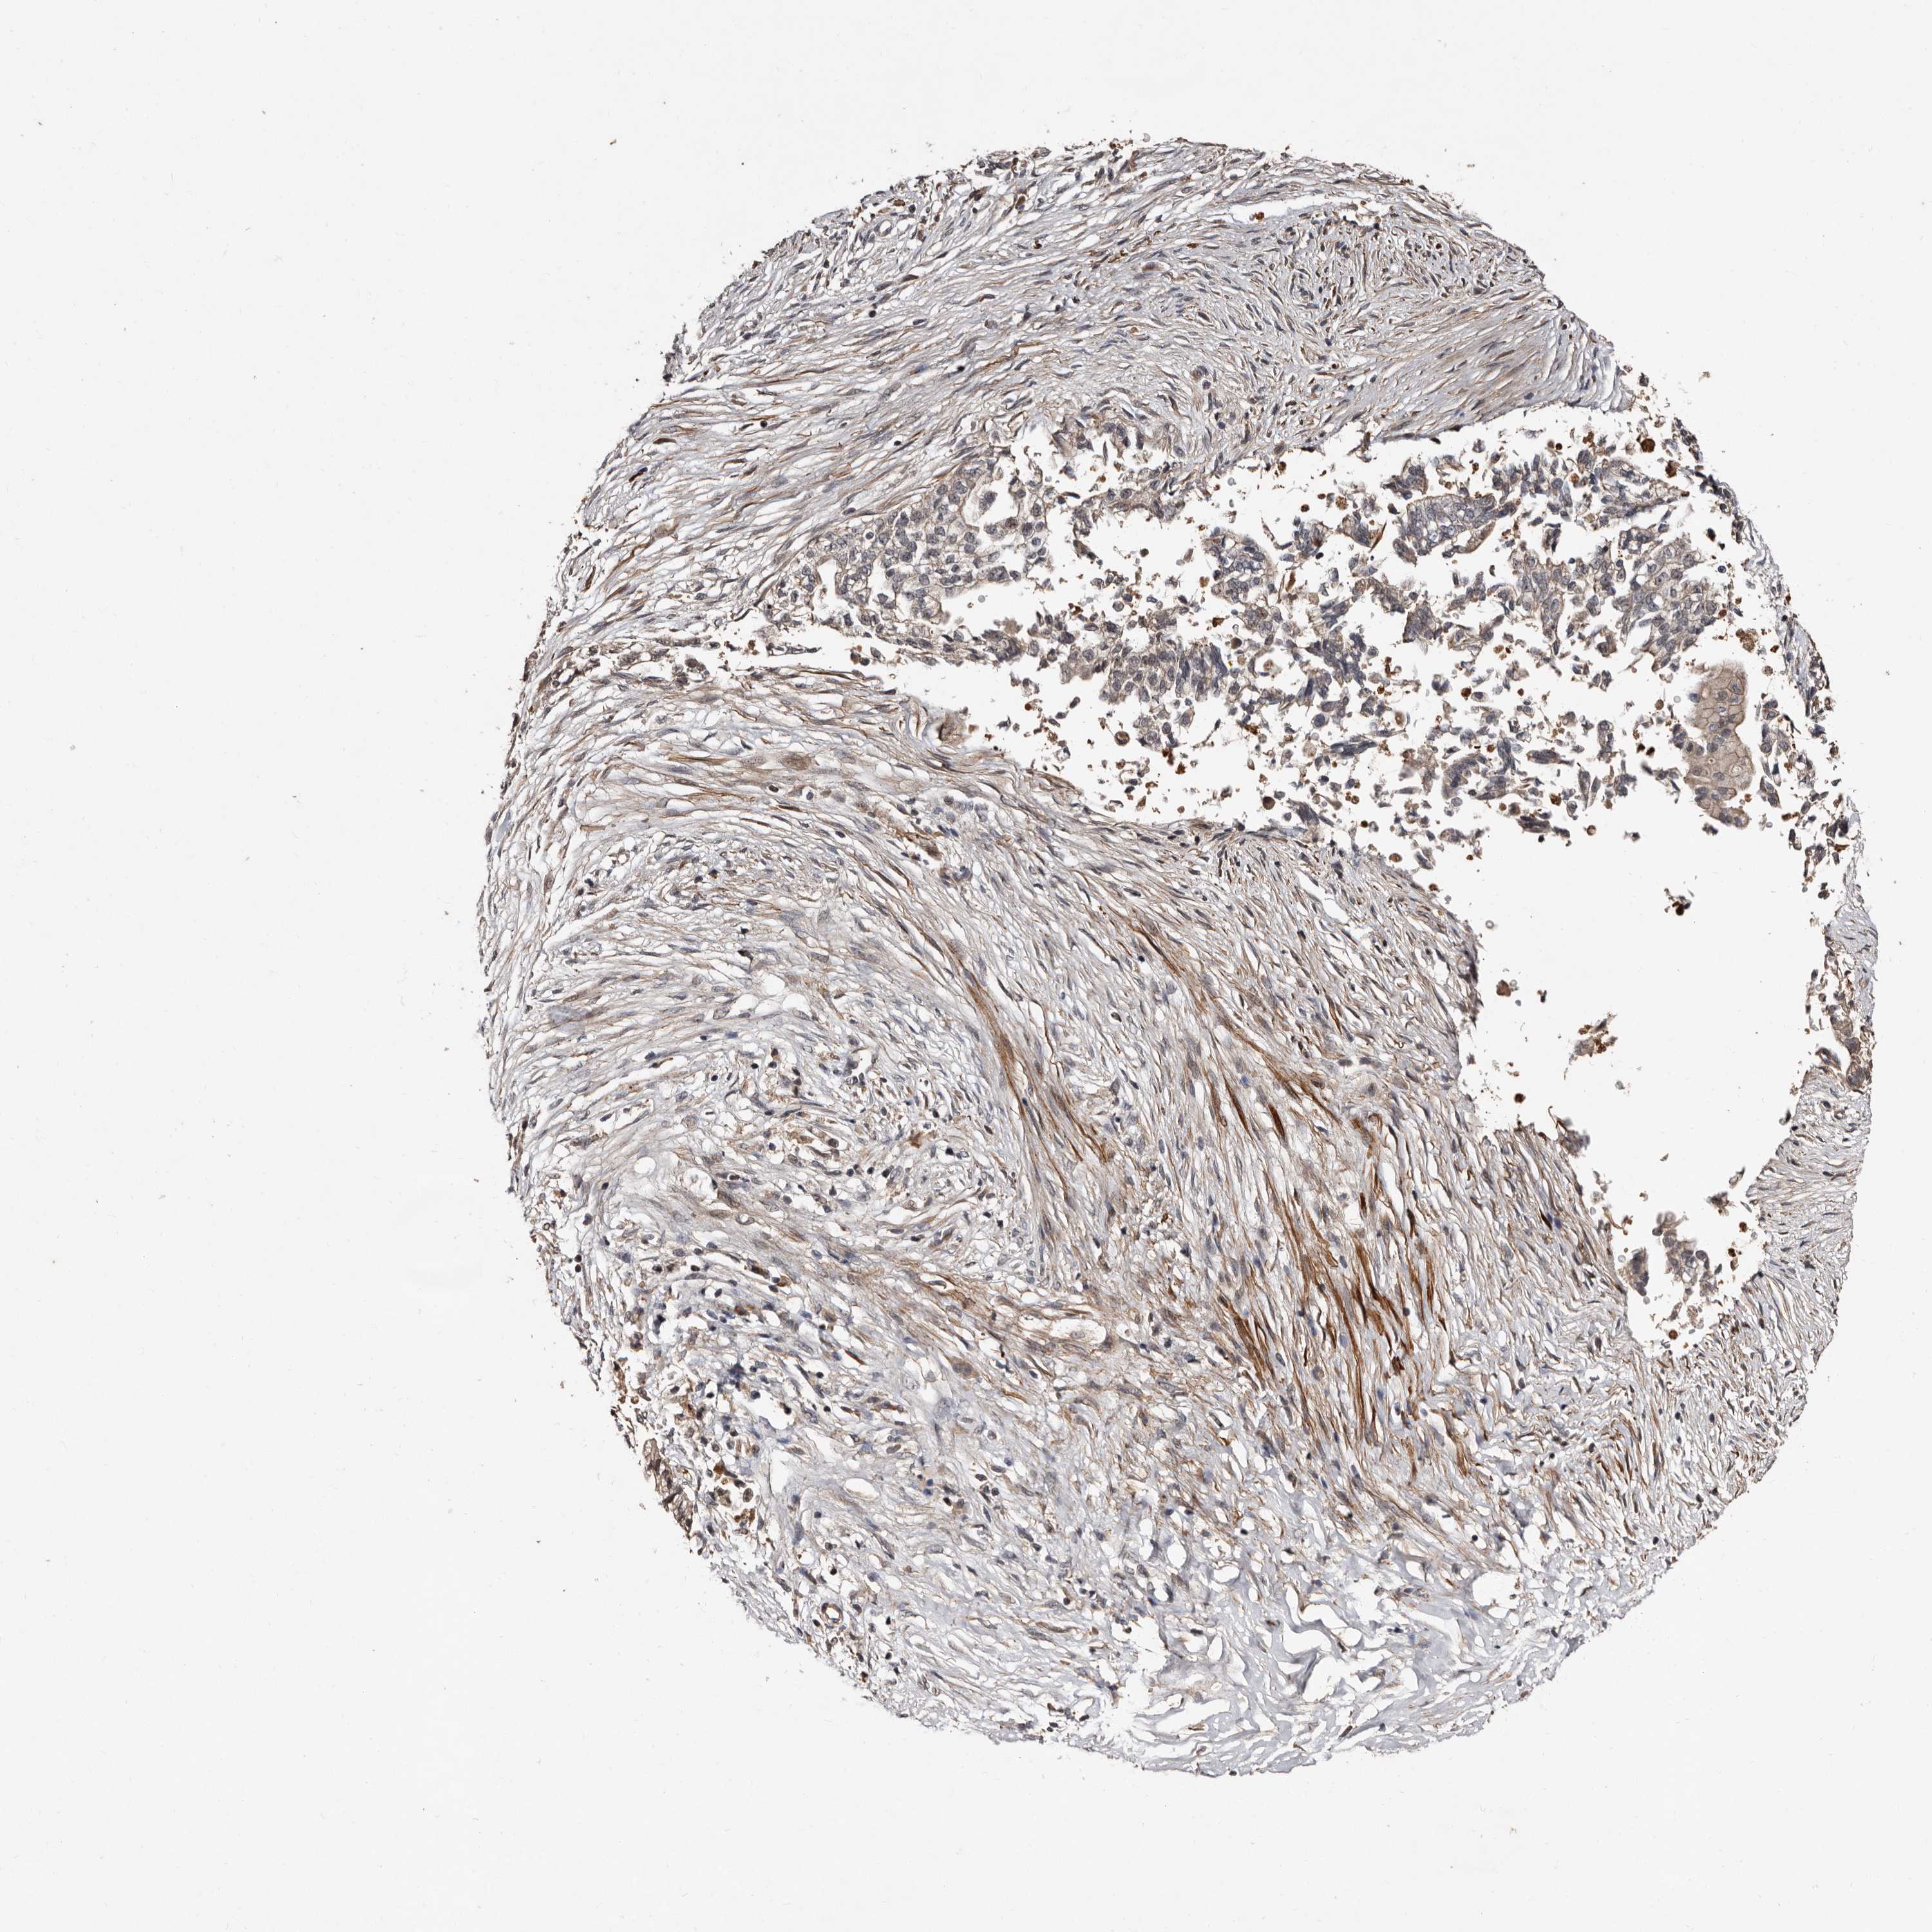

PANCREATIC CANCER - Protein expressioni

A mouse-over function shows sample information and annotation data. Click on an image to view it in a full screen mode. Samples can be filtered based on level of antibody staining by selecting one or several of the following categories: high, medium, low and not detected. The assay and annotation is described here.

Note that samples used for immunohistochemistry by the Human Protein Atlas do not correspond to samples in the TCGA dataset.

Antibody stainingi

Antibody staining in the annotated cell types in the current human tissue is reported as not detected, low, medium, or high, based on conventional immunohistochemistry profiling in selected tissues. This score is based on the combination of the staining intensity and fraction of stained cells.

Each image is clickable and will lead to virtual microscopy that enables deeper exploration of all samples and also displays staining intensity scores, fraction scores and subcellular localization as well as patient and tissue information for each sample.

Antibody HPA029529

Staining

High

Medium

Low

Not detected

Intensity

Strong

Moderate

Weak

Negative

Quantity

>75%

75%-25%

<25%

None

Location

Nuclear

Cytoplasmic/membranous

Cytoplasmic/membranous,nuclear

Adenocarcinoma, NOS